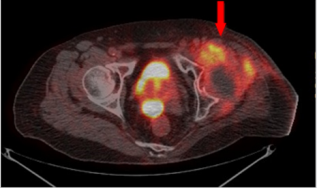

In order to correct distal femur varas deformity, we performed valgus osteotomy and fixation with Kuntsher nail (10mmx300mm), and Vancomycin-coated cement spacer at fracture site (Figure 3B). The final histopathology revealed squamous cell carcinoma. However, he complained left hip pain after bedside ambulation one week later. Radiography showed left hip subtrochanteric pathological fracture, so we exchange the Kuntsher nail with Cephalomedullary nail for fixation (Figure 3C & 3D). On the outpatient department follow-up, poor skin healing with fistula purulent discharge was still noted. Repeated MRI revealed tumor progression with involvement of gluteal muscle, anterior compartment of thigh, and left inguinal area, and the whole-body bone scan (Figure 4) had increased uptake over left inguinal area. Several debridement and tumor wide excision provided little help, so he underwent above-knee amputation. Five months later, left anterior palpable mass with anterior thigh pain and skin tenting was noted again. Repeat MRI (Figure 5) revealed recurrence of malignant tumor, lymphadenopathy in the left groin region, and peri-acetabular bone metastasis. Thus, we preceded with left hemipelvectomy (Figure 6) and skin coverage with local fasciocutaneous flap. After the surgery, the patient received adjuvant chemotherapy therapy. The pain resolved, and there was no marked local recurrence over a period of 2 years.

Figure 4: Whole body bone scan presenting increased radioactivity over anterior aspect of left inguinal area.

One hypothesis clarify that inflammatory cytokines may lead to an altered expression of tumor suppression genes causing carcinogenic transformation [6], while other hypothesis clarifies that all cell types in the chronic inflammation may be susceptible to malignant change [4]. The clinical suspicion about malignant transformation including increased in mass size, ulcers, swelling, tenderness, fistula or sinus tract discharge with odor smell, and progressive disabling pain [4,5]. Plain radiography often appears bony erosion, destruction, scalloping, or even pathologic fracture in severe cases. MRI can be useful to differentiate squamous cell carcinoma from other soft tissue tumor [3] and identify adjacent lymphadenopathy. Whole body bone scan can clarify the suspicion of distant metastasis. In our case, MRI revealed lymphadenopathy in the left groin and peri-acetabular region after primary aboveknee amputation. These finding provide us more information on the decision to perform left hemipelvectomy for tumor control.